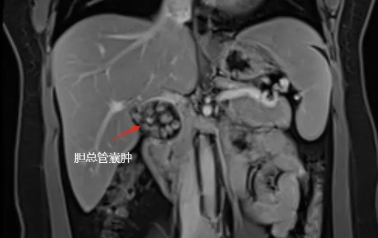

体内“定时炸弹”被拆除!广医四院腹腔镜术成功切除胆总管囊肿

胆总管内有一肿物

且里面装满胆石

最终入院后确诊为先天性胆总管囊肿Ia型,我院肝胆外科卢明柱主任团队为患者提供了详细的治疗方案——微创手术切除畸形扩张的胆管,该手术创伤小,恢复快,疗效确切,单女士欣然接受手术方案,并于近日实施了手术(腹腔镜下胆总管囊肿切除+胆囊切除+肝总管空肠Rou-en-Y吻合)。目前,单女士术后恢复良好,已顺利出院。

先天性胆总管囊肿(Congenital Choledochal Cyst,简称CCC)是一种较为罕见的先天性胆道畸形,表现为胆总管局部呈囊状或梭状扩张。该疾病多发生于儿童和青少年,女性发病率高于男性,但成人也可能患病。